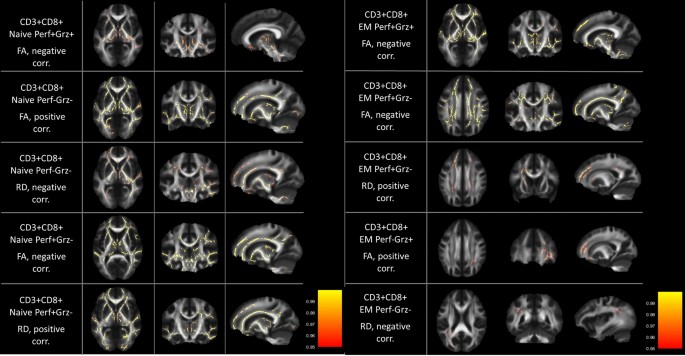

Effects were spread in the WM skeleton for Naïve, EM (Fig. 1), CM, and TEMRA (Fig. 2) cells, with signal peaks observed in Thalamic Radiation, Corona Radiata, Corpus Callosum, Superior and Inferior Fronto-Occipital Fasciculus, Forceps Minor, Internal Capsule (see detailed summary of the results in Tables 2 and 3).

WM areas where CD3+CD8+EM and CD3+CD8+Naïve cells subpopulations percentage correlated with TBSS WM indexes. Voxels of significant negative correlation are mapped on the mean FA template of the studied sample. The colour-bar refers to 1 − p values for the observed differences. Numbers are z coordinates in the standard MNI space.